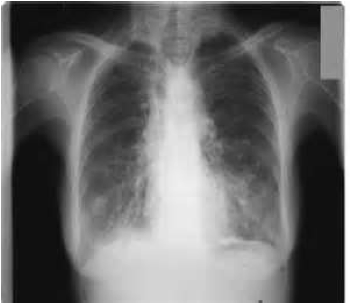

900 000 travailleurs sont potentiellement exposés à cette fibre cancérigène, les plus exposés étant ceux des chantiers de désamiantage (entre 2000 et 5000 personnes « officiellement ») ce qui est très largement en dessous de la vérité. 3000 personnes décèdent annuellement des cancers dus à l’Amiante et 100 000 sont condamnées d’ici à 2025.

Pour les Valeo Amiens, le délai est de quatre mois pour avoir le jugement de la Cour d’Appel. D’ici cette date, combien de salariés contaminés par ce poison déclaré auront-ils contactés le mésothéliome, des plaques pleurales ou l’asbestose ?